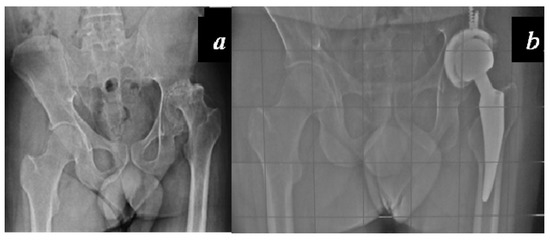

Carulli et al. reported a series of 23 haemophilic patients undergoing THA with modern cementless implants and COP couplings [1]. In 14 subjects, a standard stem was used, while in nine cases a modern short stem was adopted. No failures and no complications were recorded, with a survival rate of 100% at an 8.1-year follow-up (Figure 3 and Figure 4).

Figure 4. (a) Preoperative x-rays of the left hip of a 33-year-old patient affected by severe haemophilia A; (b) X-rays 3 years after surgery: cementless short stem, acetabular cup fixed with two supplementary screws and COP coupling.